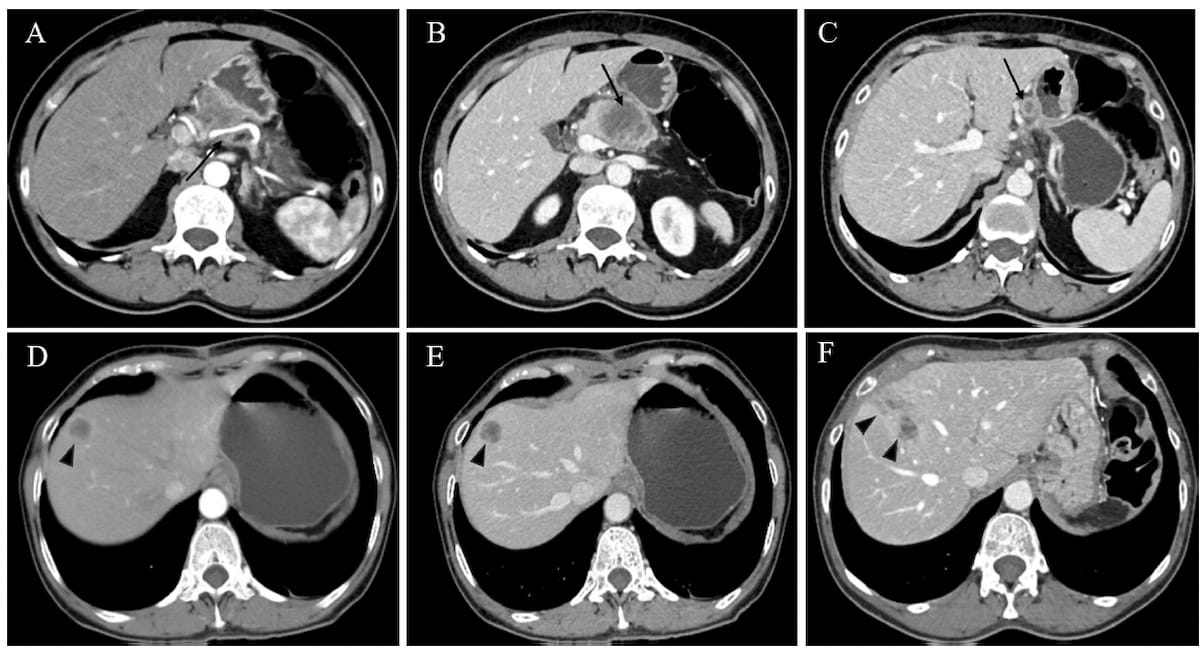

Here one can see preoperative (A-C) and postoperative CT images(D-F) for a 63-year-old woman, who had an early recurrence score (ERS) of 45 as per an emerging risk stratification system for predicting recurrence of pancreatic ductal adenocarcinoma after radical resection. Post-op CT images acquired at 63 days (E) and 155 days (F) reveal the development and growth of hepatic metastases. (Images courtesy of European Radiology.)